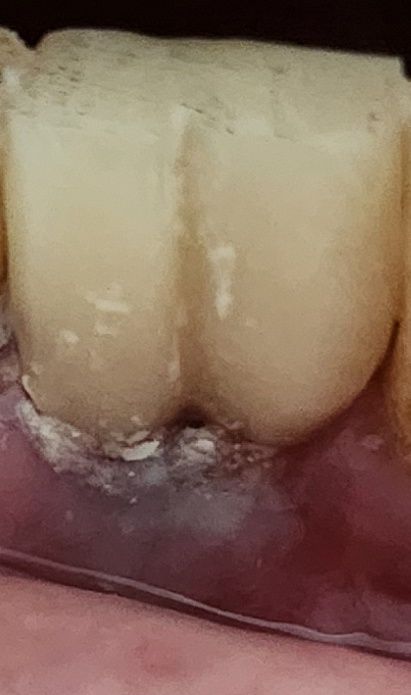

안녕하세요. 뼈이식과 임플란트 식립 3개월 후, 어제 다시 잇몸을 절개하여 지주대를 세우고 임시치아를 부착했습니다. 임플란트 뿌리만 식립하고 회복하는 동안 핑크 빛으로 예쁘게 아물어 있었는데, 어제 지주대 시술 및 임시치아 부착 후 잇몸이 사진과 같이 회색빛으로 보입니다. 잇몸이 부족해서 지주대나 뿌리가 비치는 걸까요? 잇몸에 염증이 생긴걸까요? 통증은 없으십니다.

• 1번 째 사진

사진에 보이는건 임시치아 접착제가 남은거거나 임시치아를 다듬은 재료가 남아 잇는거 같으니 치과에 가셔서 체크를 받아보세요.

현재 붓기나 출혈이 없는 상태에서 회색빛으로 보이는 것은 염증가능성은 낮으며, 지주대나 임플란트 뿌리가 잇몸을 통해 비쳐 보이는 증상일 가능성이 높습니다. 문제가 되는 증상은 아니며, 만약 통증 및 붓기 동반시에는 반드시 치과 진료를 받길 권합니다.

잇몸이 얇아 비쳐보이는 경우도 있습니다. 다만 현재 사진만으로는 판별이 어렵고 일단 치간 사이, 잇몸에 낀 이물질, 잔여 시멘트, 치태는 제거하고 봐야 할 것 같습니다. 잔여 시멘트는 염증 유발의 주된 원인입니다.

임플란트 보철물 내부에 금속이 있다면 금속색이 밖으로 비쳐나와 보이면서 어둡게 볼 수 있습니다. 잇몸이 자라 오류가 오게 되면 괜찮아지는 경우가 있기 때문에 잇몸이 아무는 것을 지켜보는 것이 좋습니다. 자세한 확인을 위해서 치과에서 진료를 받아보는 것을 권해드립니다.